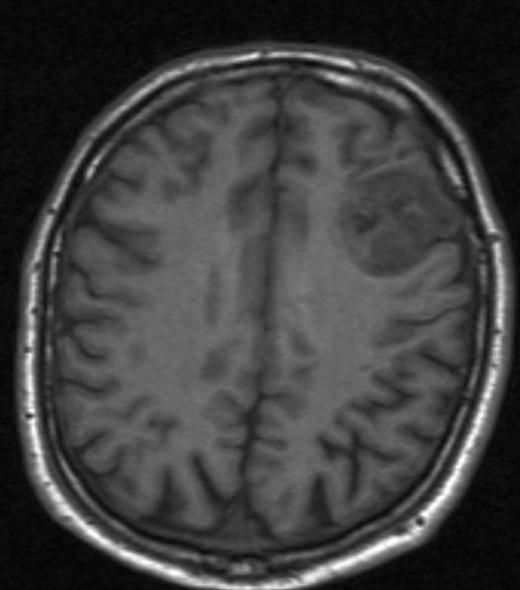

Oligodendrogliom, aksialt snitt

Gjengitt med tillatelse av Radiologisk avdeling, Universitetssykehuset Nord-Norge